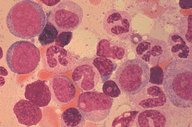

This low oil magnification view of a bone marrow

aspirate, stained with Romanofsky stain, shows

primarily myeloid precursors ranging from

myeloblasts to segmented neutrophils. Several

erytroid precursors with condensed nuclear

chromatin are also seen.